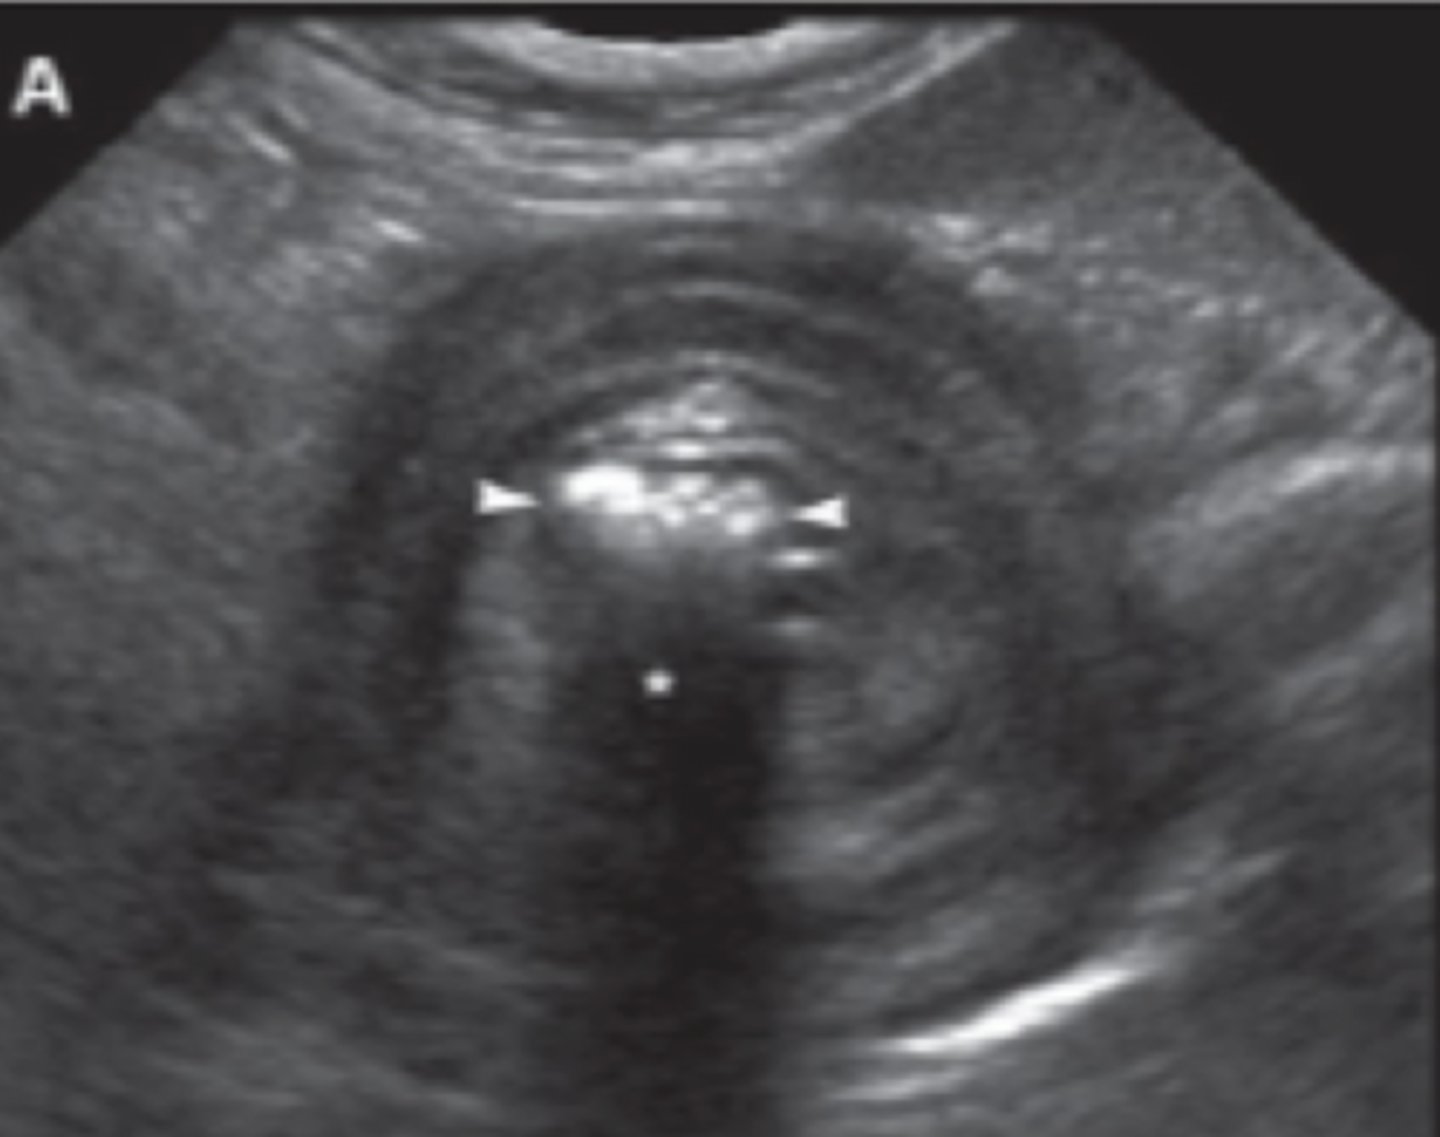

colelitos

(opacidad mineral, nivel hígado)

patología:

(hiperecoico, con sombra)

barro/ sedimento biliar

(más hiperecoico en la vesicula biliar)